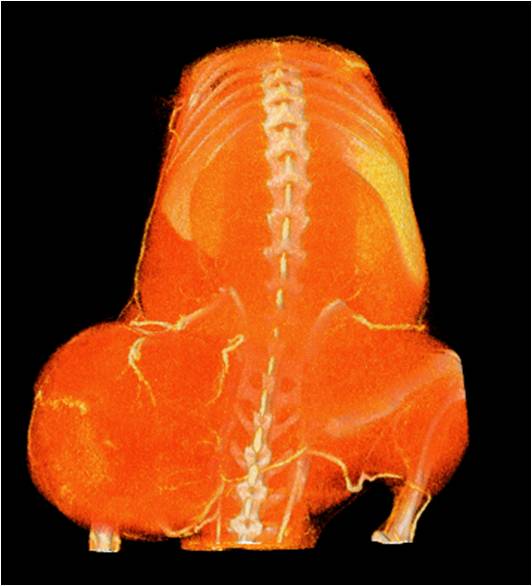

胸部和心血管的層析成像 胸部和心血管的3D圖像

心血管.jpg 心血管1.jpg